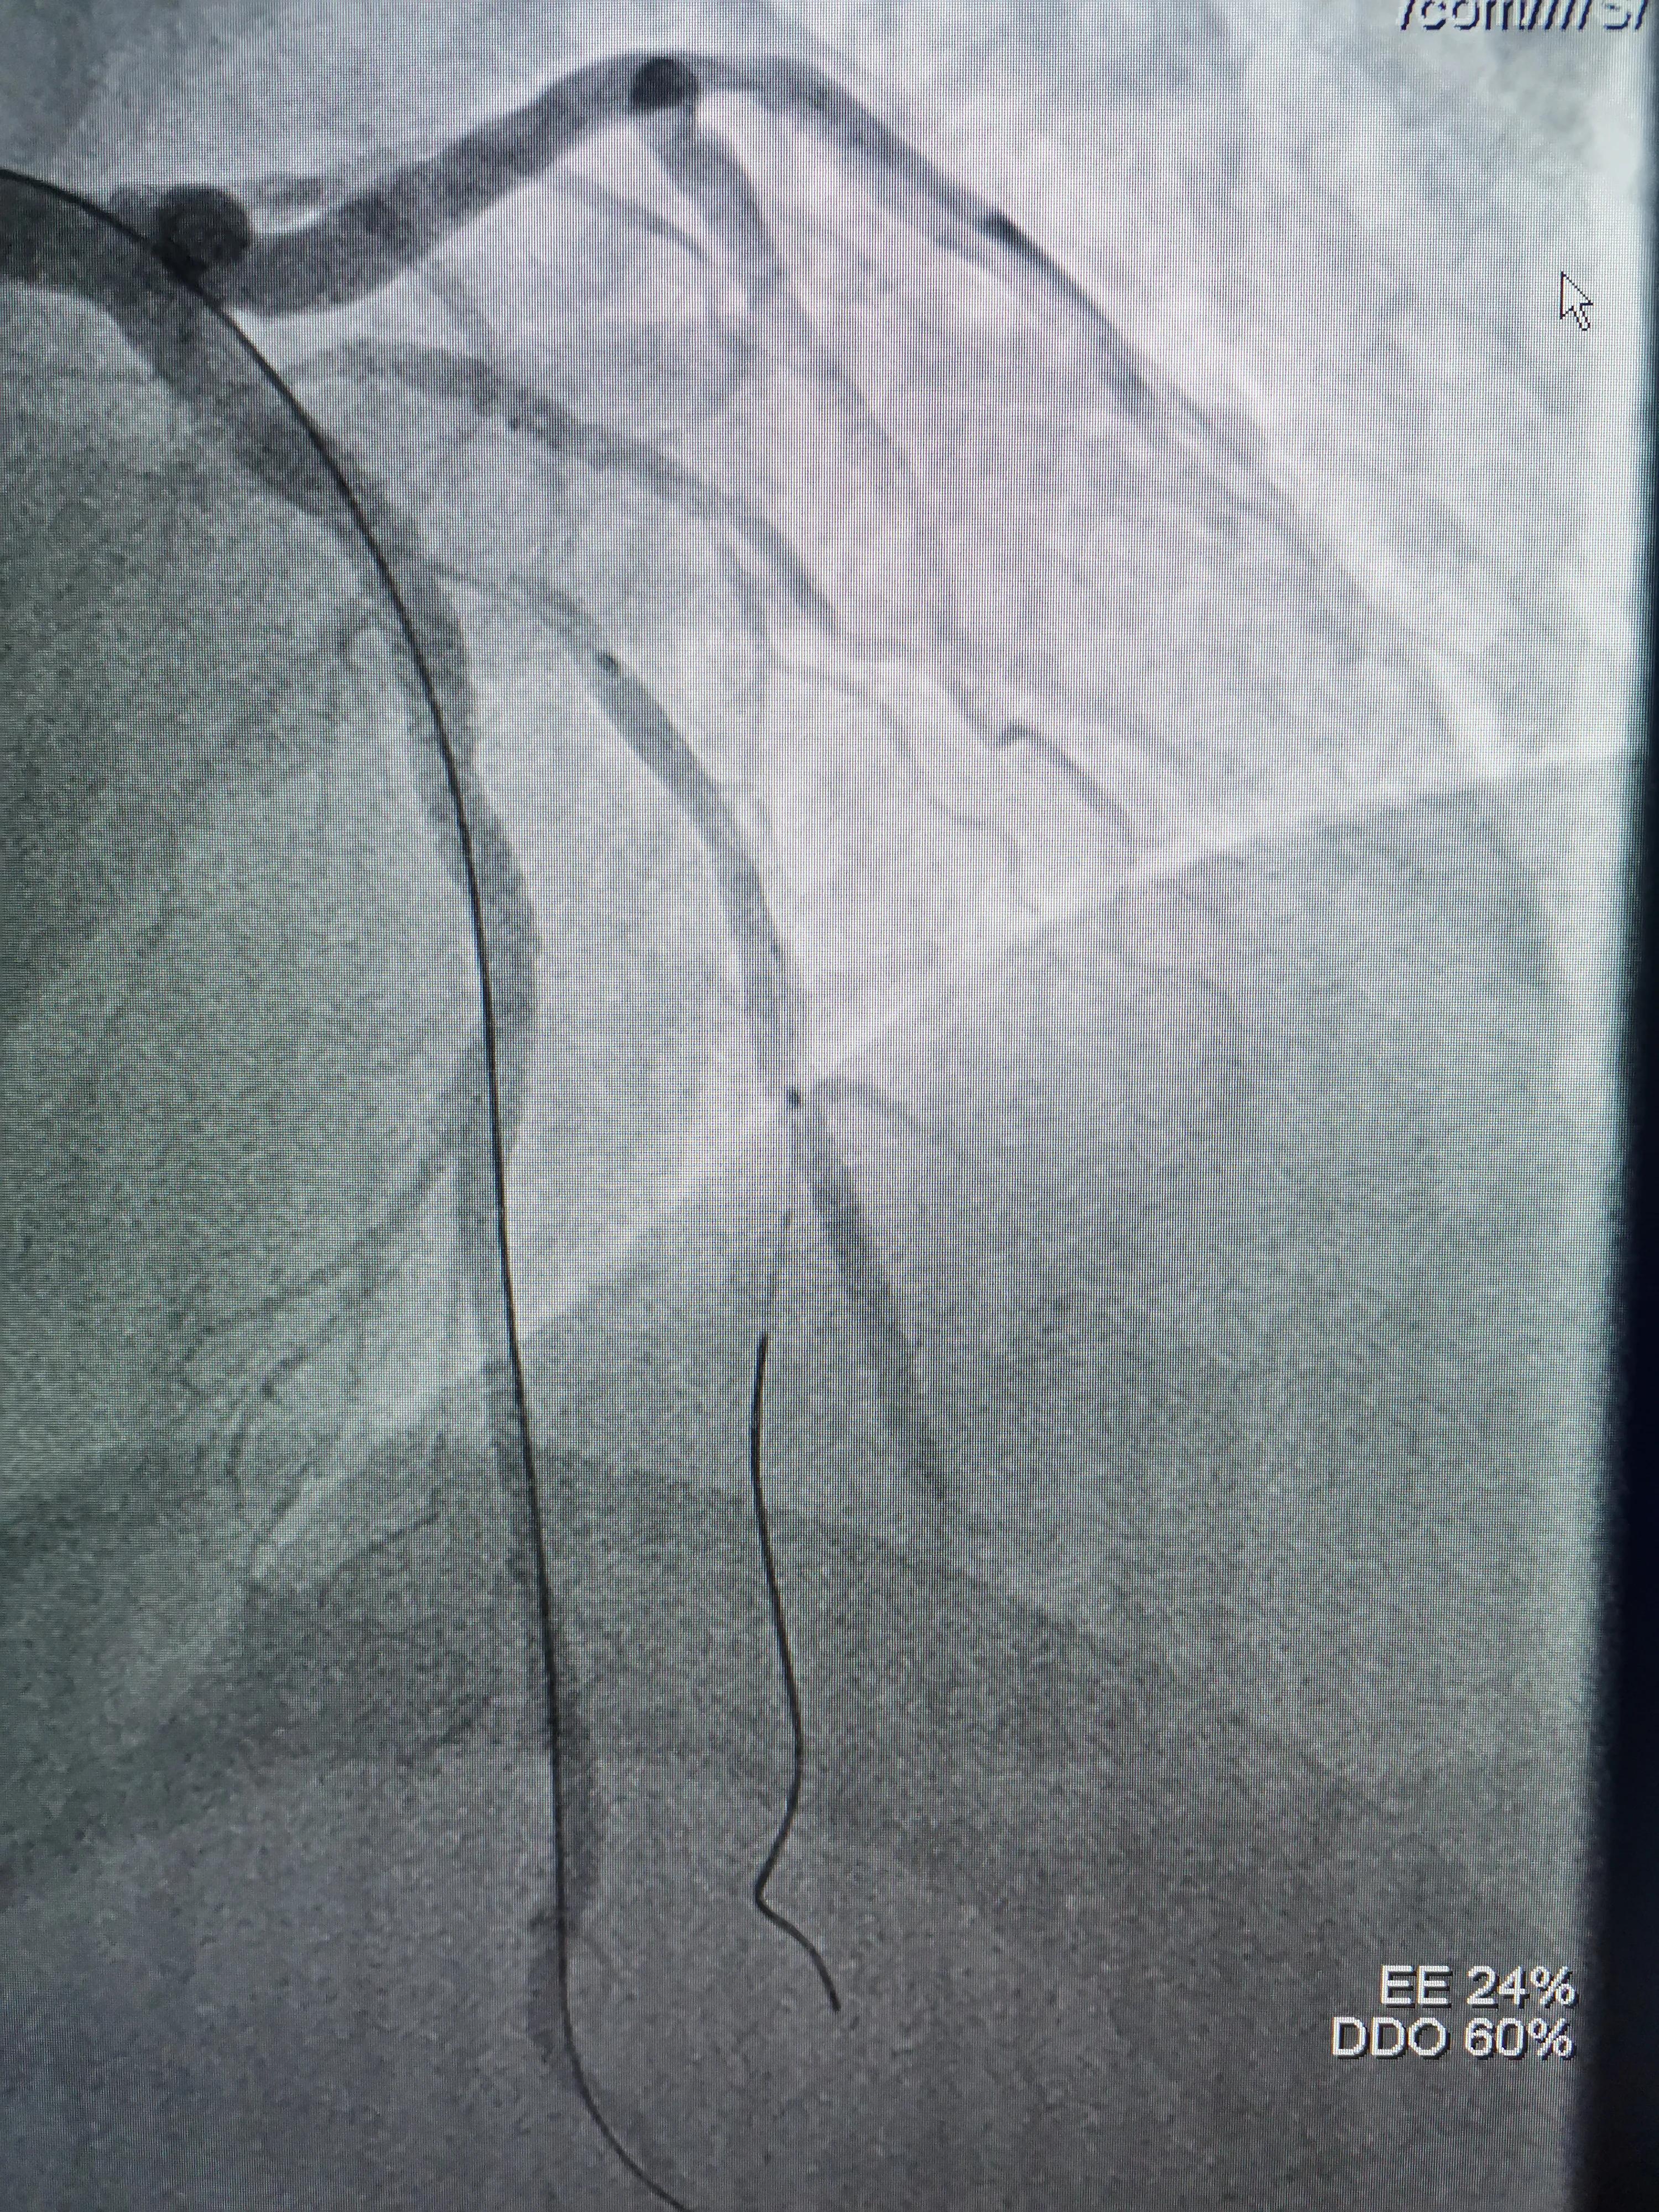

(造影发现D1开口明显受累)

(预置在D1球囊在开口处扩张)

(因血管落差较大,支架近段用3.5mm球囊优化扩张)

复查造影,支架完全贴到血管壁,分支开口受累狭窄消失,影像效果满意决定分支不再植入支架,结束手术。